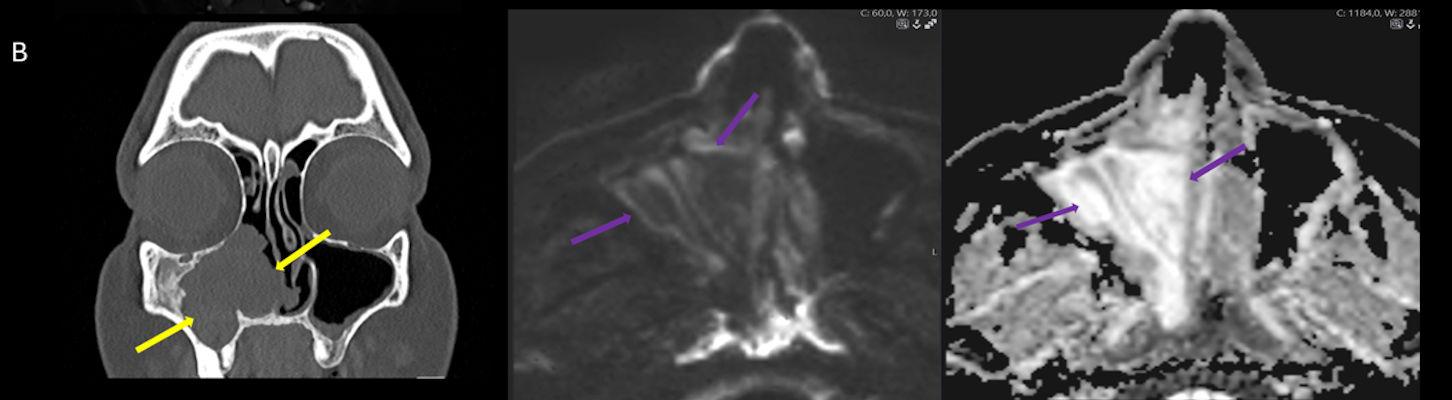

- A) Koronal T2 ağırlıklı görüntülerde sol maksiller sinüs lümenini dolduran, belirgin ‘convoluted’ (karmaşık-kıvrımlı) serebriform patern sergileyen lezyon (oklar), kontrastlı seride heterojen ve yoğun kontrastlanma göstermektedir (oklar). Perfüzyon incelemesinde pedinkülünde perfüzyon artışı gösterdiği, diğer kontrastlanan segmentlerin nispeten hipoperfüze olduğu görülmektedir (ok).

- B) BT incelemesinde maksiller sinüsün duvarları özellikle lateralde daha belirgin olmak üzere reaksiyonel kalınlaştığı izleniyor (oklar). DWI ve ADC haritasında lezyonda belirgin bir kısıtlılık görülmemektedir (oklar).

- Tümörün köken aldığı bölgede fokal hiperostoz görülebilir. Sinüs duvarlarında erozyon olabilir ancak bu genellikle tümör basısına veya eşlik eden inflamasyona sekonderdir, direkt invazyon kesin değildir. Kalsifikasyon beklenen bir bulgu değildir (olursa atipi veya malign transformasyon akla getirilmeli)

- MR incelemesinde sinonazal inverted papilloma tipik olarak T2 ve post-kontrast T1 serilerde ‘convoluted’ serebriform paternde heterojen sinyal ve kontrastlanma gösteren, pedinküler orijininde daha belirgin perfüzyon artışı sergileyen, genellikle difüzyon kısıtlaması izlenmeyen ve komşu sinüs duvarlarında ekspansiyona bağlı remodelinge yol açabilen benign ancak lokal agresif karakterde bir yumuşak doku kitlesi olarak izlenir.